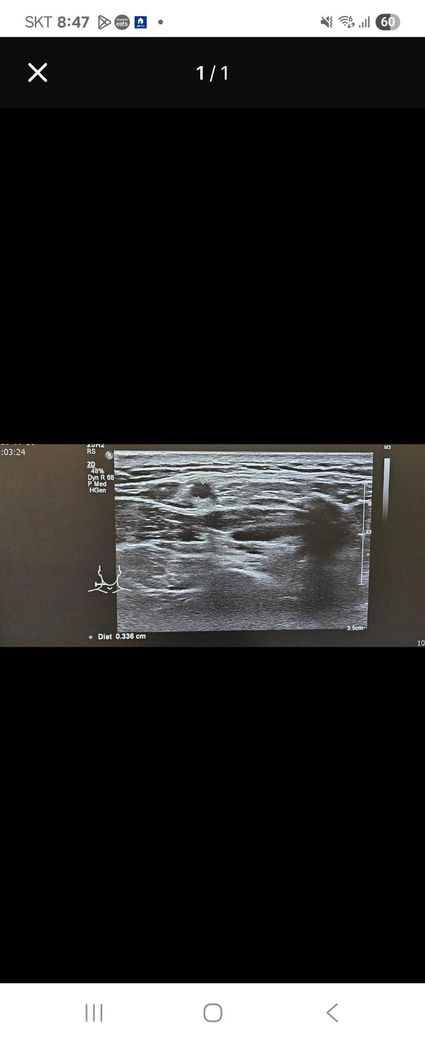

목 임파선 초음파좀 뵈주세요......

동그란데 크기가 작다고하셔습니다...

저거말고도 여러개있는데 다른건

모양이 괜찮다고 하셨습니다

• 1번 째 사진